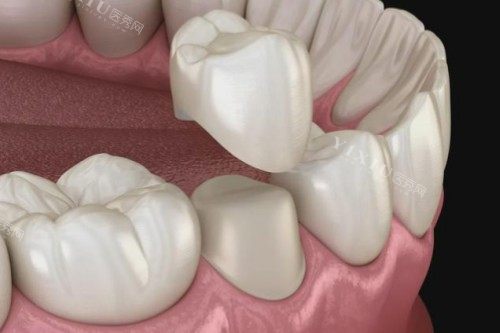

牙冠镶牙价格

镍铬烤瓷牙:500 元起

钴铬烤瓷牙:800 元起

二氧化锆烤瓷牙:1200 元起

纯钛烤瓷牙:1600 元起

国产爱尔创全瓷牙:1800 元起

国产爱迪特全瓷牙:2000 元起

德国威兰德全瓷牙:2500 元起

德国泽康全瓷牙:3500 元起

美国 3M 拉瓦全瓷牙:6500 元起

瑞士全瓷牙:10000 元起

国产氧化锆全瓷冠:1400 元起